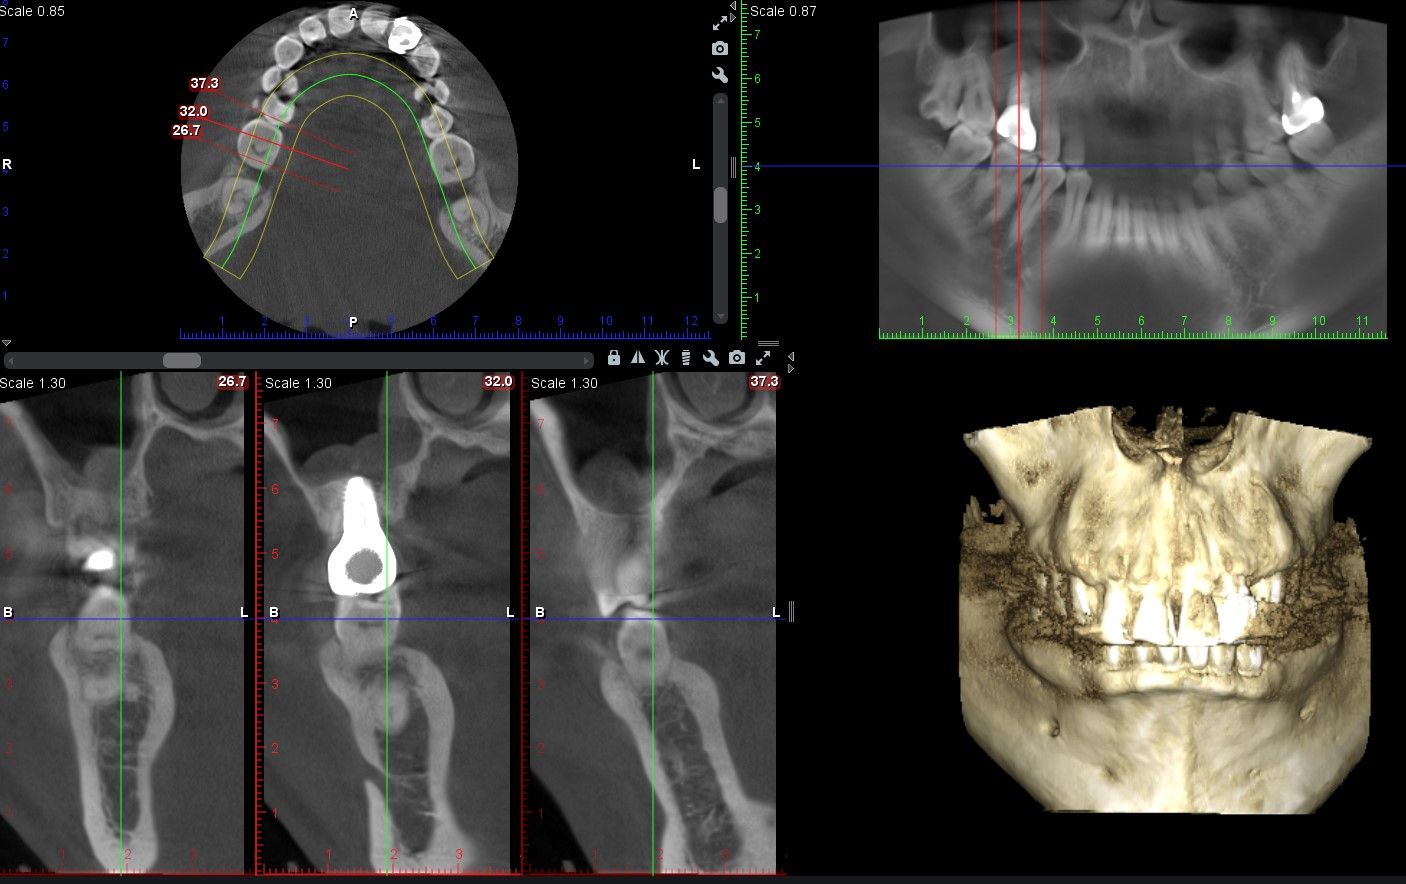

上顎竇增高 前後比較

術後電腦斷層